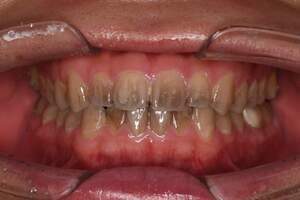

歯石除去

治療前

治療後

| 年齢 | 36歳・男性 |

| 主訴 | 歯石をとりたい |

| 治療内容 | 歯石除去 |

| 治療期間 | 30分 |

| 費用 | 約2,000円 |

| リスク・副作用 | ・歯ぐきの炎症が強いと歯石を取る際に出血することがあります。 ・処置後に歯がしみることがあります。 ・歯と歯の間に隙間ができるので、息が漏れ発音しにくいと感じることがあります。 ・歯ぐきの炎症が軽減すると歯ぐきが引き締まり、歯が長く見えることがあります。 |